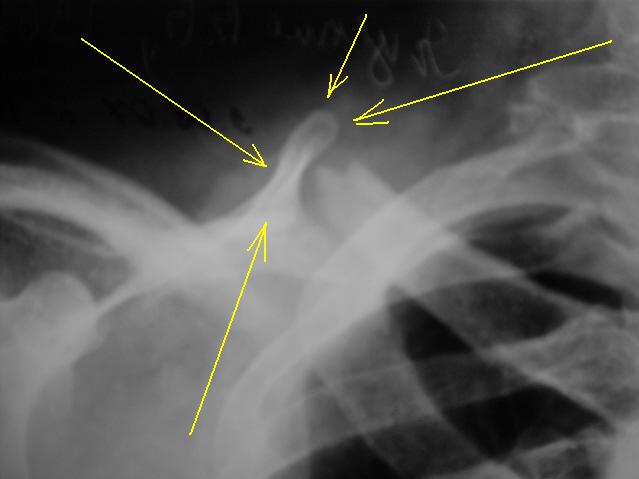

А как трактовать помеченное желтыми стрелками?

А это верхний угол лопатки. Такое впечатление, что он образует с проксимальным отломком ключицы что-то типа неоартроза.

Вот мне тоже примерно такое и кажется, но что-то не совсем мне понятно.

А что, все очень похоже......есть "импровизированная" суставная впадина, образовавшаяся из верхнего угла лопатки, и с ней сочленяется отломок ключицы, все довольно конгруэнтно

Как-то мне не кажется убедительным наличие ложного сустава. Почему-то наружный край внутреннего отломка ключицы неровный, остренький, совсем не выглядит суставной "головкой". Да и край лопатки не так, чтобы деформирован, не склерозирован. Может быть это проекционно такое близкое расположение получается? А край лопатки просто вышел на край, потому что вся лопатка смещена и повернута (ключицей не удерживается?).